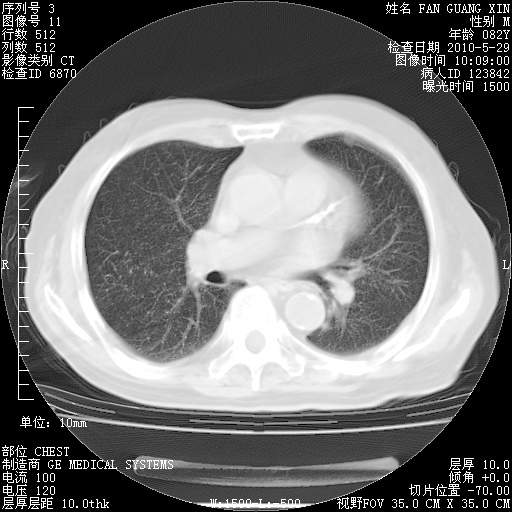

还需要哪些辅助检查?我们医院排除真菌感染没有任何检验方法,胸片好像能够排除肺部真菌感染。

补充:ENA化验全部阴性。免疫五项(IgG、IgA、IgM、C3、C4)只有C4略高。

CD3+ T细胞/淋巴细胞 46% (参考值50.00~84.00%)

CD3+CD4+ T细胞/淋巴细胞 21% (参考值27.00~51.00%)

CD3+CD8+ T细胞/淋巴细胞 25% (参考值15.00~44.00%)

CD3+CD4+ T细胞/CD3+CD8+ T细胞 0.84 (参考值0.71~2.78)

T细胞亚群是治疗5天采血。